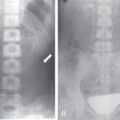

Amit Kumar Kamble, Abhinav Ranwaka The adult urinary system is formed of a pair of kidneys, a pair of ureters, a urinary bladder and a urethra. All these structures are extraperitoneal in location and extend from upper abdomen to the pelvis and into the exterior. These organs can be visualised on a host of imaging modalities, and a knowledge of these appearances helps the radiologist identify the relevant pathologies. Having a complex embryological development, the urinary system can have a wide spectrum of normal and abnormal anatomical variants. This chapter describes the appearance of the urinary system in commonly used imaging modalities and their common variants. Kidneys are paired bean-shaped structures situated in the retroperitoneum on either side of the vertebral column. The kidney consists of The renal sinus contains: The kidneys are surrounded by the renal capsule which is enclosed in the perirenal space. This space predominantly contains the perinephric fat and has thin septations within (Kunin’s septa); these septae may be thickened in various renal pathologies seen as perinephric stranding on imaging. The perirenal space is bounded by the perirenal fasciae, called the Gerota fascia (anterior perirenal fascia) and Zuckerkandl fascia (posterior perirenal fascia). The leaves of perirenal fascia fuse superiorly, laterally and medially. Superiorly, the perirenal fasciae also enclose the adrenal gland, which is separated from the kidney by a septum (Fig. 10.2.2). The anterior and posterior perirenal fasciae fuse laterally to form the lateral conal fascia. Medially, the perirenal fascia also encloses the renal pedicle. Medially, it communicates with renal sinus fat. There may be the communication of perirenal spaces across the midline. Superiorly, the perirenal space communicates with the bare area of the liver or spleen. The ureter arises from the perirenal space and travels inferiorly in anterior pararenal space. Inferiorly, the perinephric space may communicate with periureteric tissues. Interfascial planes are potential planes in between the leaves of the anterior perirenal fascia, called the retromesenteric plane and in the anterior perirenal fascia called the retrorenal plane. Anterior pararenal space: It is bounded by parietal peritoneum anteriorly, anterior perirenal fascia (Gerota) posteriorly and lateral conal fascia laterally. The anterior pararenal space contains the pancreas, second and third part of the duodenum, the retroperitoneal segments of ascending and descending colon and the roots of the small bowel mesentery and transverse mesocolon. Posterior pararenal space: It is bounded by posterior perirenal fascia (Zuckerkandl) anteriorly, fascia transversalis posteriorly and lateral conal fascia laterally. Caudally, the pararenal spaces communicate with each other and also with the extraperitoneal spaces. All the three spaces communicate at the pelvic brim. Understanding of the anatomy of spaces around the kidney is important for local staging of renal pathologies. Renal arteries are the branches of abdominal aorta. They originate laterally from the aorta below the origin of superior mesenteric artery. Accessory unilateral renal artery occurs in 30% of the population and bilaterally in 10% of population. Renal artery is divided into anterior division, which divides into four segmental branches and a posterior division; these arteries are end arteries supplying the respective segments of the kidneys (Fig. 10.2.3): apical, upper, middle, lower segments supplied by the anterior division, and a posterior segment supplied by the posterior division. The segmental arteries divide into lobar branches one to each to renal pyramid. Before reaching to pyramid, they divide into two to three interlobar branches. At the junction of cortex and medulla, interlobar arteries divide into arcuate arteries at the right angle. They further subdivide into interlobular artery, afferent and efferent arterioles. The efferent arteriole drains into peritubular plexus. The plane where the branches of the anterior and posterior divisions meet is located between the anterior two-thirds and posterior one-third of the kidney and is relatively avascular; it is called the avascular plane of Brodel (Fig. 10.2.3), and is a relatively safe site for nephrostomy access. Peritubular plexus converges to form the interlobular vein. These veins accompany their arterial counterparts and drain into the renal vein. The renal veins are situated anteriorly to the renal arteries and finally drain into the inferior vena cava at the right angles (Fig. 10.2.4). The two left renal veins may be present one passing anterior and other posterior to the aorta known as persistence of renal collar. Sometimes a single retroaortic left renal vein (Fig. 10.2.5) may be present. Supernumerary right renal vein may be seen. Renal vein variations are more common on the right side. The lymphatics of the kidneys drain into the lateral aortic nodes at the level of origin of renal arteries. Normal kidneys may be visualised on a frontal abdominal radiograph as faint oval shadows on either side of the vertebral column immediately besides the psoas shadows (Fig. 10.2.6). On contrast radiography and intravenous urography, the renal shadows show gradual opacification, peaking between 30 and 60 seconds followed by opacification of the pelvicalyceal system on subsequent radiographs. The kidneys are visualised in longitudinal and transverse views usually by placing the probe in the loin with the patient in supine or lateral position. The normal kidneys appear less echogenic than the liver and show a thin echogenic capsule. The surface of the kidney is usually smooth in adults, and may be lobulated in infants and young children. The renal parenchyma shows an outer cortex, which generally shows a uniform thickness, surrounding the less echogenic medullary pyramids, with invaginations of the columns of Bertin between the medullary pyramids (Fig. 10.2.7). This differentiation between the echogenicity of the cortex and medulla is called corticomedullary differentiation, which is lost in certain disease states. The renal pyramids are most hypoechoic compared in infancy gradually becoming less hypoechoic with age. The hypoechoic renal pyramids may at times be confused for hydronephrosis by an inexperienced observer. Arcuate arteries may be identified in some adults between the cortex and medulla as linear echogenic lines (Fig. 10.2.8A) and should not be mistaken for calculi. The renal sinus is seen as a central hyperechoic area of the kidneys owing to the presence of fat. The renal calyces and pelvis are not visualised normally as they are collapsed. They may sometimes be seen if the bladder is overdistended, a finding which reverses once the patient emptied the bladder. Doppler interrogation allows evaluation of the renal vasculature in great detail. The renal artery, its segmental, interlobular and arcuate branches and the corresponding veins can be easily visualised (Fig. 10.2.8B). At the renal hilum, the renal vein lies anterior to the renal artery. The right renal artery is longer and lies posterior to the inferior vena cava (IVC). The left renal vein crosses midline and courses in between the aorta and superior mesenteric artery. On CT scan (Fig. 10.2.9), the kidneys are well identified and well demarcated owing to the presence of surrounding fat. They show a homogeneous appearance with intermediate density between 35 and 55 HU on non-contrast CT scan with a central low-density renal sinus.